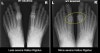

AP view, lateral view X-ray 사진에서 발허리발가락관절 간격이 좁아지며, 엄지의 발등 및 가쪽면에 골극이 보입니다.

X-ray : 무지 강직증(Hallux rigidus)